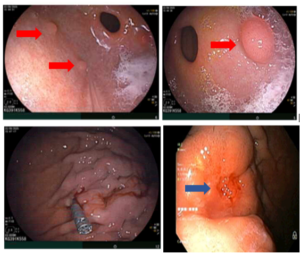

CASE LÂM SÀNG “HIỆU QUẢ ĐIỀU TRỊ UNG THƯ PHỔI KHÔNG TẾ BÀO NHỎ GIAI ĐOẠN MUỘN BẰNG OSIMERTINIB TẠI BỆNH VIỆN BẠCH MAI”

CASE LÂM SÀNG “HIỆU QUẢ ĐIỀU TRỊ UNG THƯ PHỔI KHÔNG TẾ BÀO NHỎ GIAI ĐOẠN MUỘN BẰNG OSIMERTINIB TẠI BỆNH VIỆN BẠCH MAI” GS.TS. Mai Trọng Khoa, PGS.TS Phạm Cẩm Phương, TS. Phạm Văn Thái, ThS. Hoàng Công Tùng, BSNT. Nguyễn Thanh Nguyệt Trung tâm Y học hạt nhân...